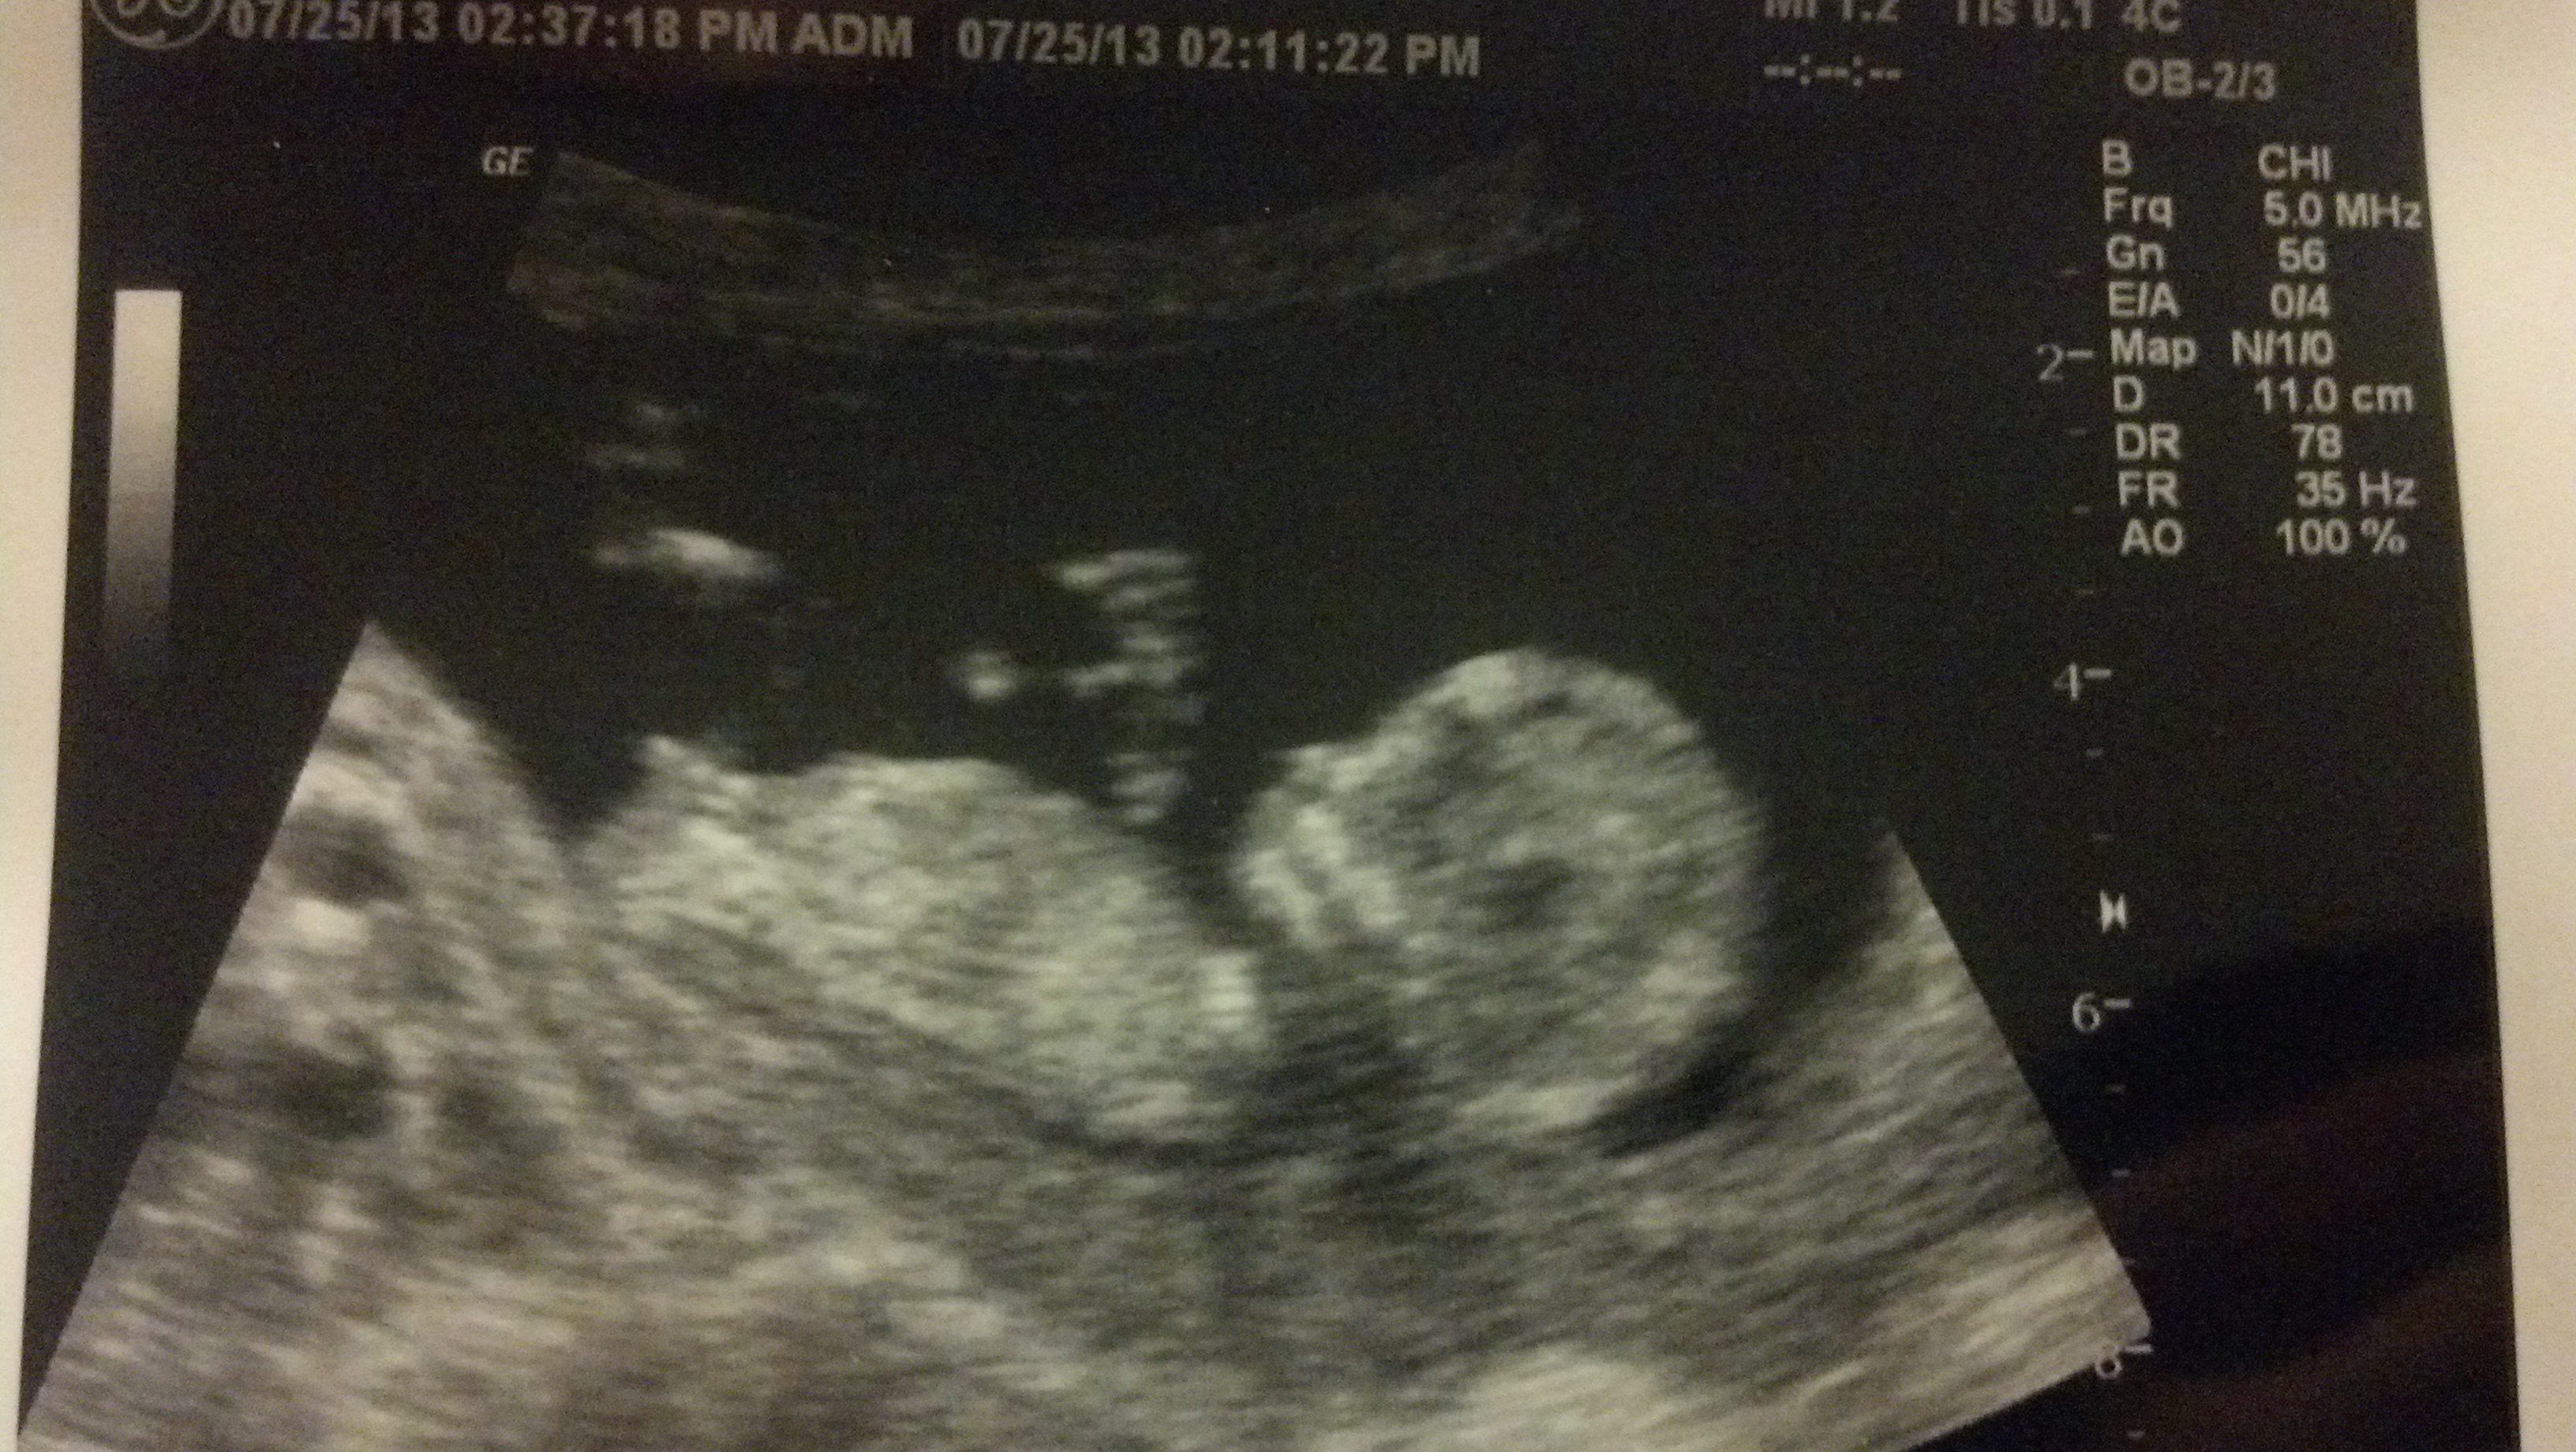

I go in a cpl weeks for an early gender prediction scan but this was my 13 week scan. Any guesses?